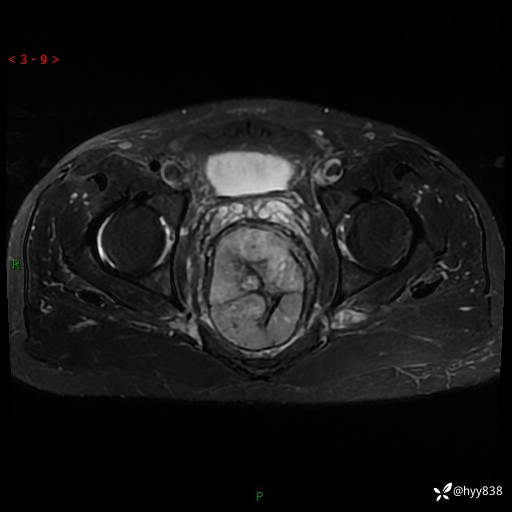

盆腔MRI平扫